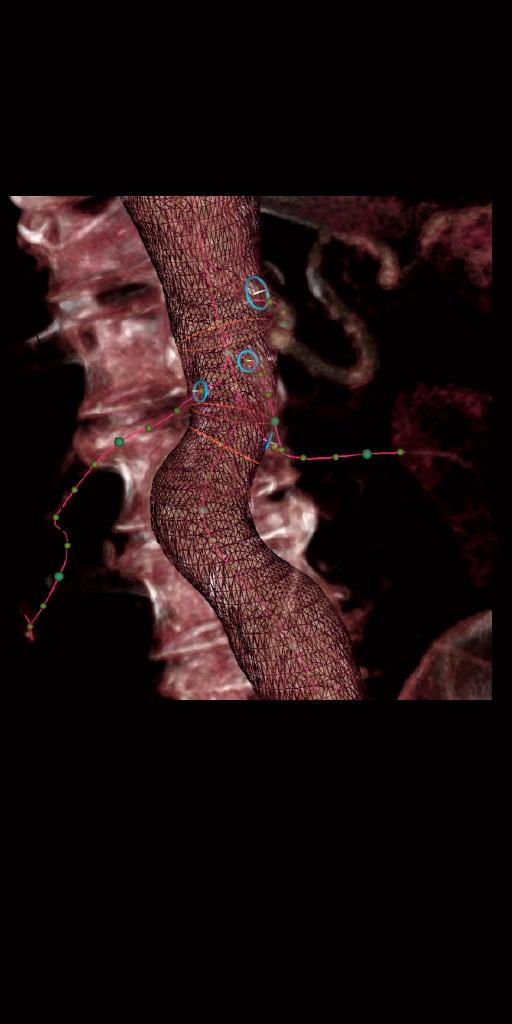

syngo EVAR Guidance

Ce logiciel améliore le flux de travail afin que vous puissiez vous concentrer sur le déploiement des endoprothèses (angles de l’arceau optimisés, superposition précise d’informations 3D et aide à la navigation du guide et du cathéter).

Pour commencer, EVAR Guidance prépare automatiquement les images TDM pré-procédurale,

comme la segmentation et mise en place

des zones d’intérêt anatomiques.

syngo 2D/3D Fusion

syngo 2D/3D Fusion recale le

volume 3D issu du TDM pré-procédural avec la position du patient le jour J pour

faciliter la superposition des

informations 3D et la position de l’arceau.

Pendant la procédure, syngo EVAR Guidance ajuste

automatiquement l’angle de l’arceau afin d'optimiser la superposition et

d'obtenir une vue perpendiculaire des vaisseaux sélectionnées.

syngo DynaCT

Utilisez syngo DynaCT

pour évaluer le déploiement des endoprothèses à la fin de la procédure EVAR.

L’assistant 3D facilite la sélection du protocole d'imagerie, le

post-traitement optimal et les paramètres d’injection.